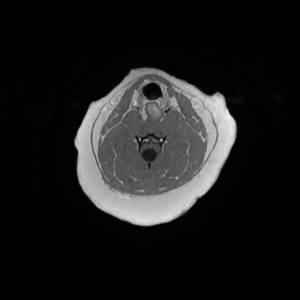

Main Gallery

Playing with a photo gallery function. It is possible to have multiple galleries, each within a namespace.